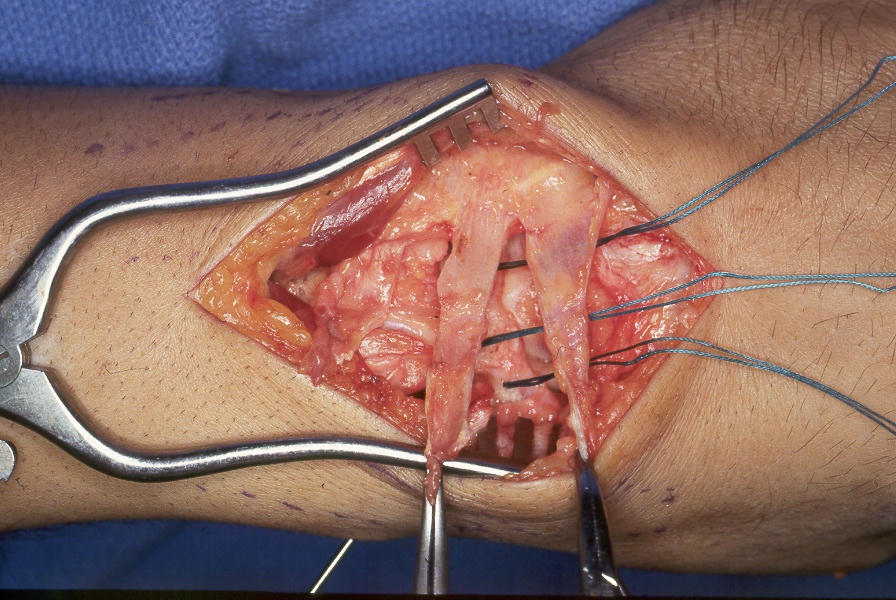

Case 2. Direct repair of scapholunate ligament and retinaculum  transfer (Ragnell retractor beneath). (Right hand, fingers to the right)

Click for larger image